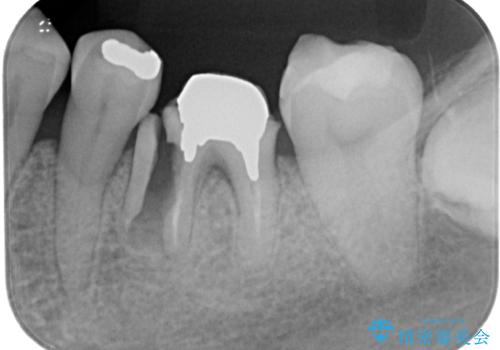

当院では、他院で抜歯と言われてきた歯を何とか保存する治療を多く行ってきましたが、レントゲン上で確認できるほど割れてしまっている歯はさすがに要抜歯と説明をし、インプラント治療を行うこととしました。

下顎大臼歯の抜歯即時埋入インプラント治療では、複数ある歯根のうち、後方の歯根部にインプラントを埋入することで一般的であり、今回破折して骨吸収が著しいのは前方の歯根であったため、事前に仮歯を用意した上で、抜歯即時埋入インプラントによる補綴治療を行うこととしました。